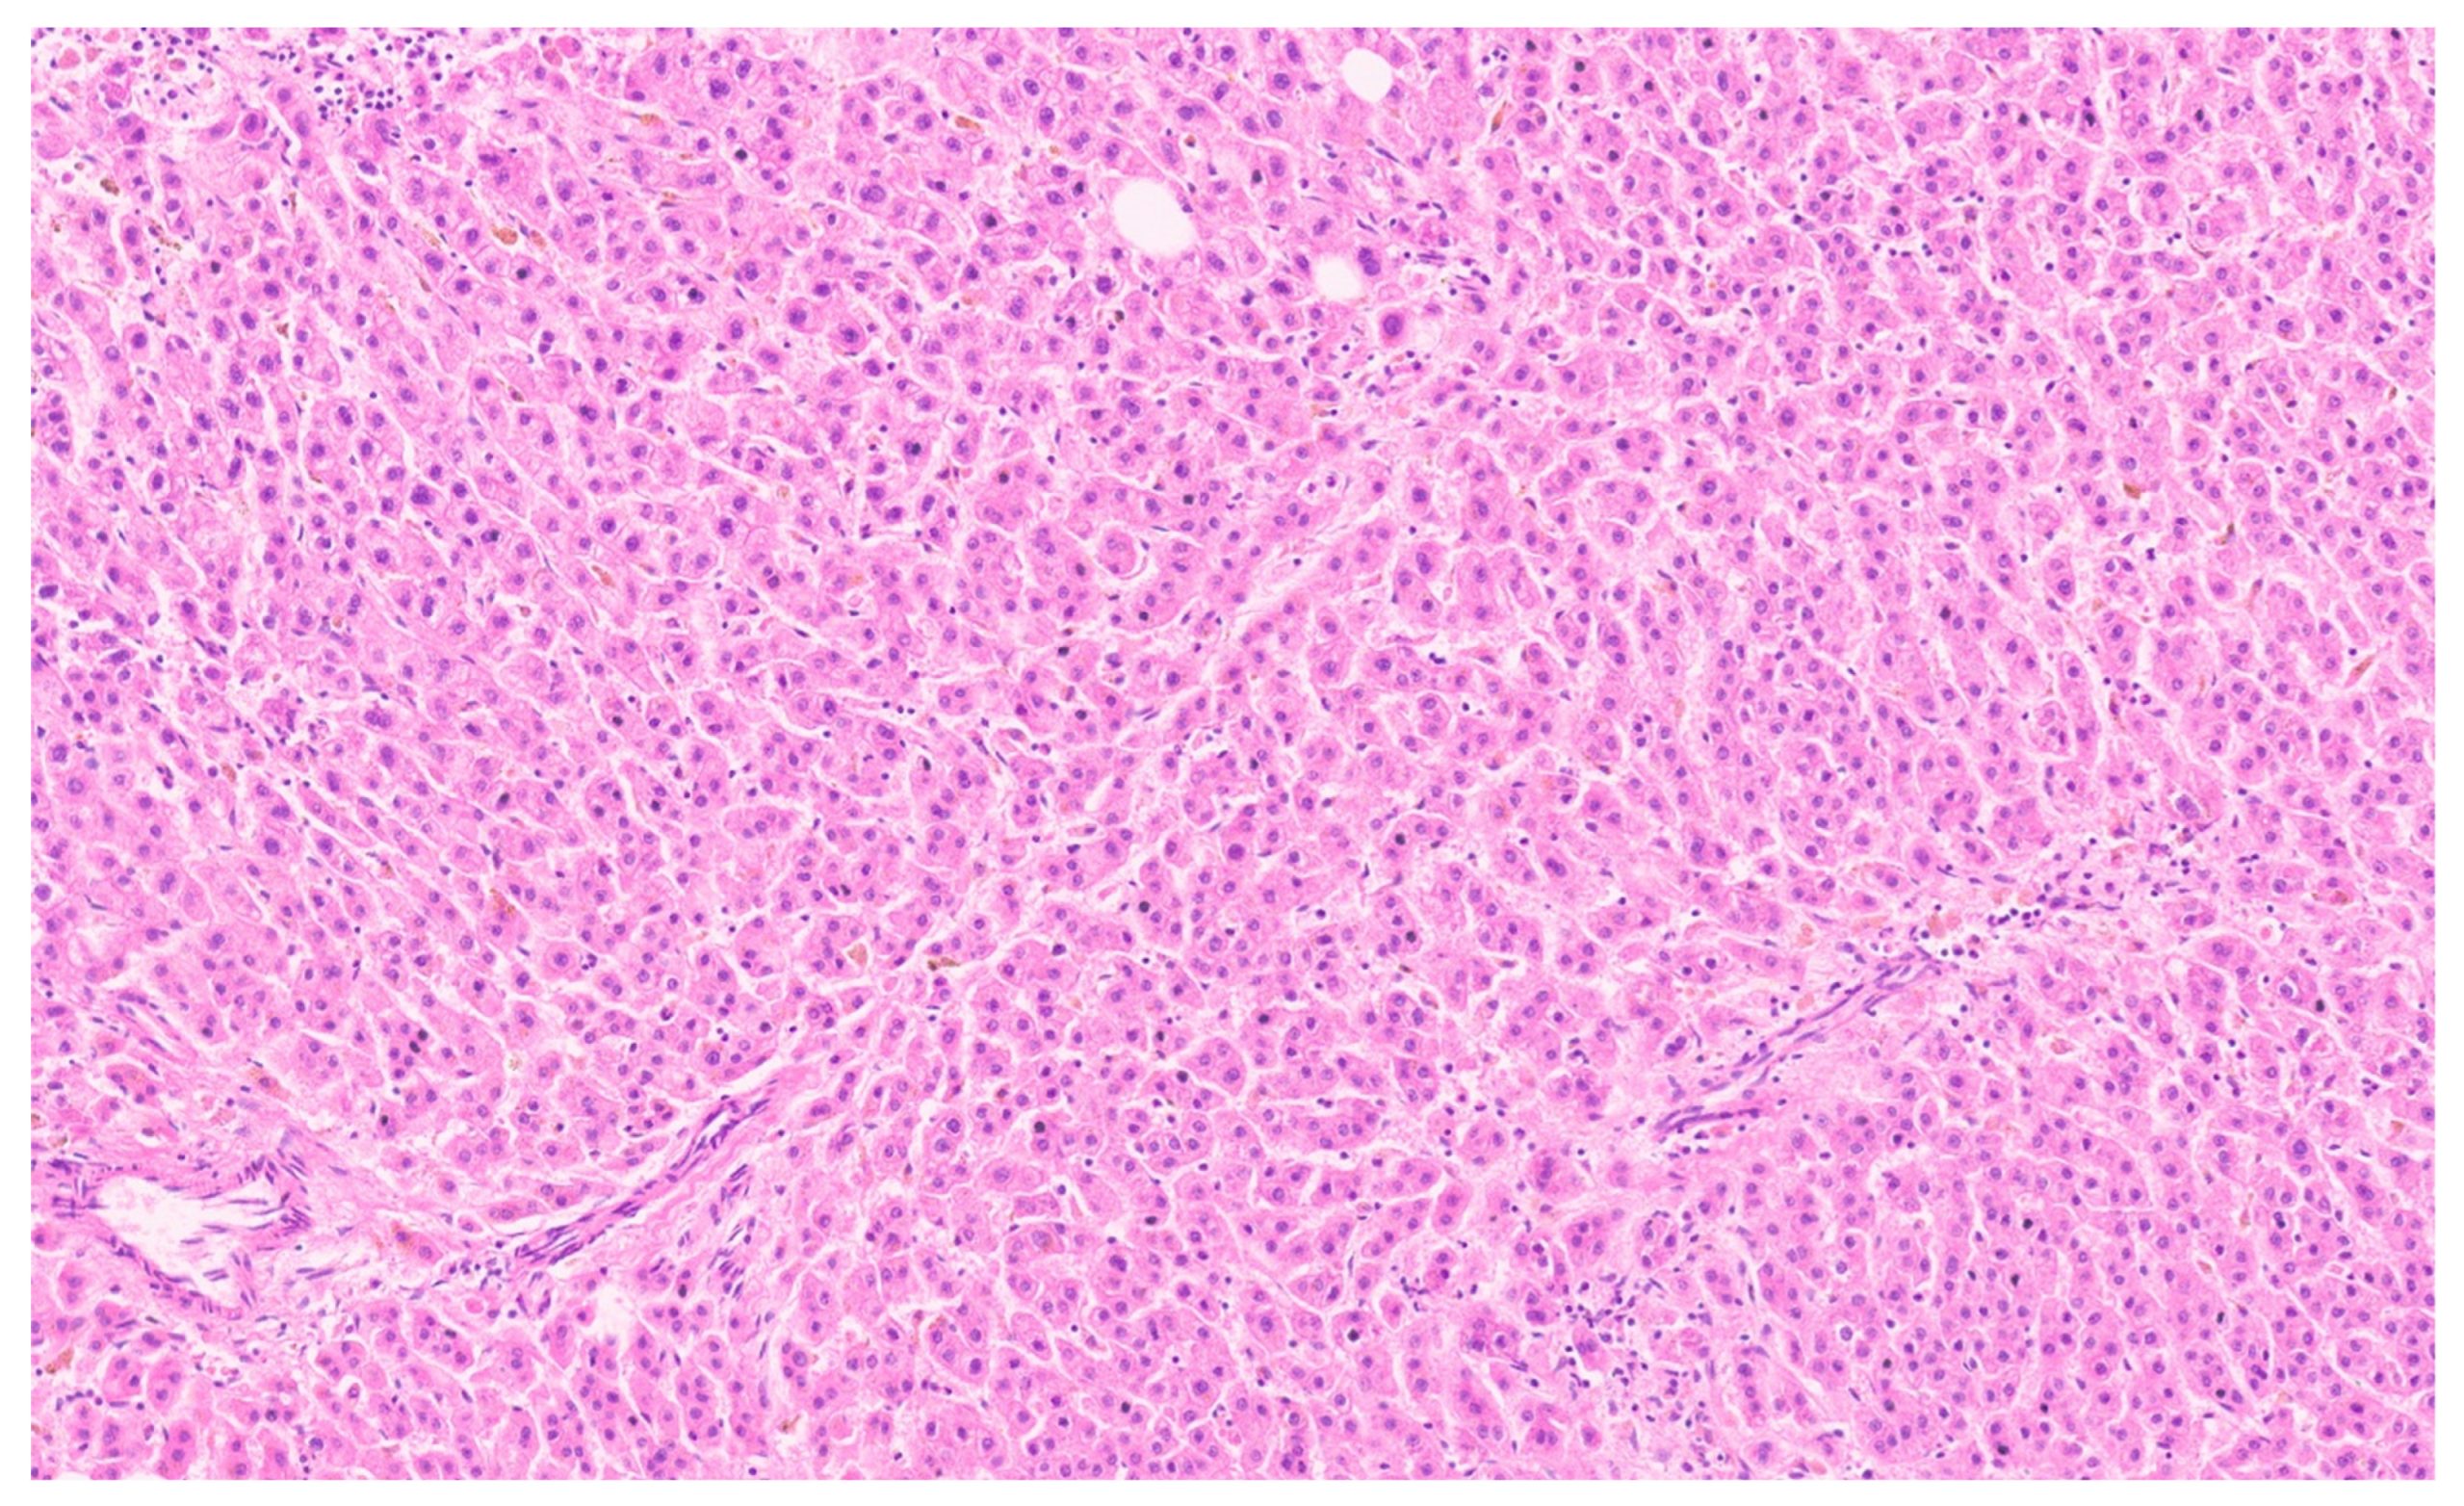

16.3. Pathology

| Histopathology | Well Differentiated | Moderately Differentiated | Poorly Differentiated |

|---|---|---|---|

| Arrangement | Trabeculae that are at least 3 cells thick and lined by sinusoids, pseudoacinar arrangement | Trabeculae that are 15–20 cells thick lined by sinusoids, pseudoacinar arrangement | Sheets or nests of cells not resembling hepatocytes. |

| Cells and nuclei | Resemble hepatocytes with mild nuclear pleomorphism, centrally placed round nuclei, and abundant cytoplasm | Moderate nuclear pleomorphism, large nuclei with prominent nucleoli and intranuclear inclusions, abundant cytoplasm. | High N/C ratio, nuclear pleomorphism, prominent nucleoli and intranuclear inclusions, numerous mitosis |

| Necrosis | Usually absent | May be seen | Present |

| Immunohistochemistry | Variable glypican 3 and glutamine synthetase levels. Negative for β-catenin nuclear staining | Glypican 3 and glutamine synthetase are positive in 50% of cases, β-catenin is variable | Glypican 3 and glutamine synthetase |